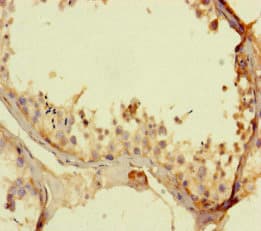

Anti-TALK1 antibody(ab234652)

Rabbit Polyclonal TALK1 antibody. Suitable for IHC-P and reacts with Human samples. Immunogen corresponding to Recombinant Fragment Protein within Human Potassium channel subfamily K member 16 aa 250 to C-terminus.

Applications IHC-P

Species Reactivity Human